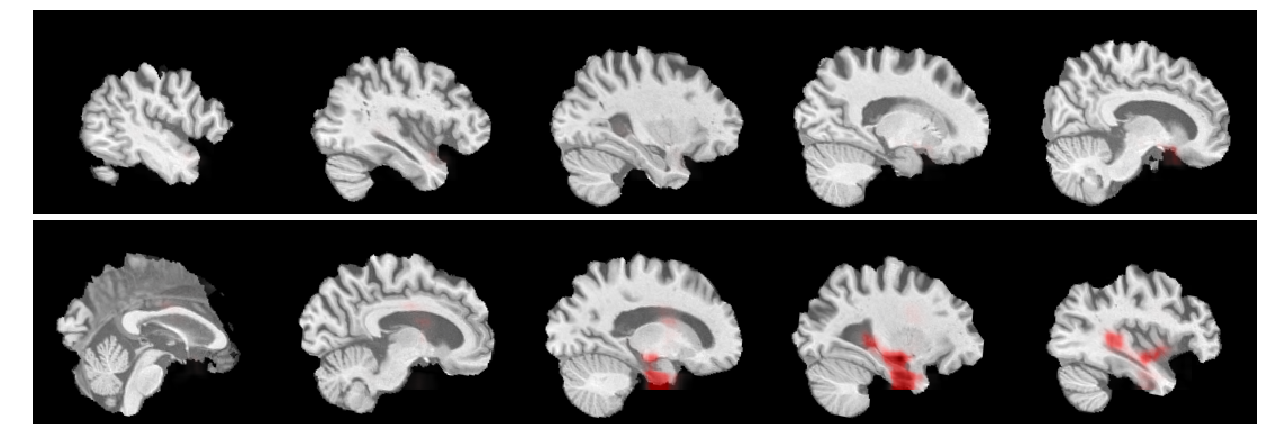

Refer to caption

Figure 3: Visual assessment (best viewed in color): ST explanation for a sample true positive image shown in ten equally spaced sagittal slices displayed from left to right and top to bottom. Here the model focused on the left hippocampus and ventricles.

V-C Qualitative Analysis of Visual Explanations

To visually check the quality of the heatmaps generated by our proposed visual explanation approach, we take one MRI scan for visual inspection and present the corresponding heatmaps. Figure 3 shows the ST explanation for a sample image of an AD patient that was correctly classified using AlexNet 2D++C. The 3D image is shown in sagittal slices displayed from left to right and top to bottom. These heatmaps should be read as an indication of where the network model sees evidence of AD. As can be seen, the model uses meaningful patterns as a basis for its decision, since the heatmaps correlate with what is known from the literature. Specifically, the network assigned importance the left hippocampus and ventricles.